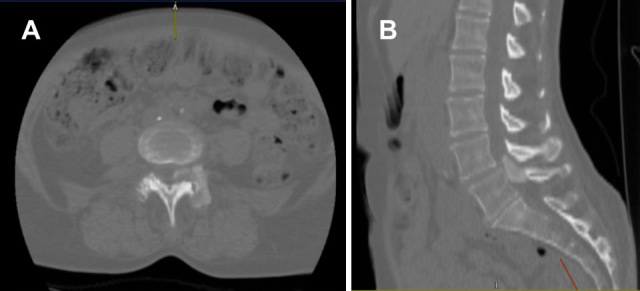

Severe Spinal Stenosis Secondary to a CREST Syndrome Related Calcific Deposit: A Case Report.